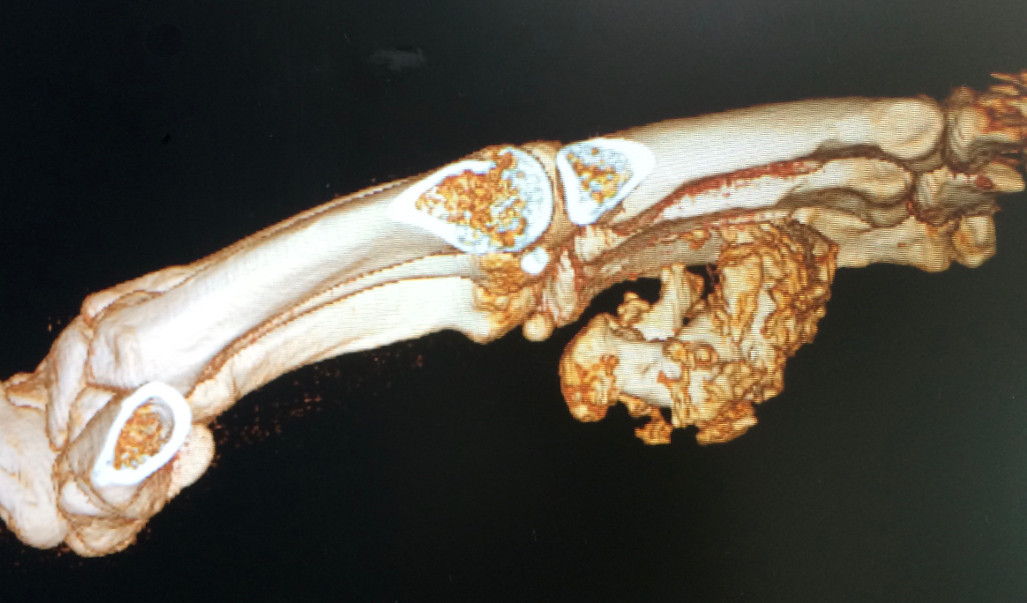

Rheumatoid arthritis affects the cells that line and normally lubricate the joints. This is a systemic condition which affect the whole body, and may affect multiple joints, usually on both sides of the body. The synovium becomes inflamed and erodes the cartilage and bone. The swollen tissue may also stretch the surrounding ligaments resulting in deformity and instability. The inflammation may also spread to the tendons, this resulting in stretching out of and ruptures of the tendons. Rheumatoid arthritis of the hand is most common in the wrist and the finger MP and PIP joints

Rheumatoid arthritis affects the joints (synovial tissue). It is a systemic disease, which means that it can affect many joints, usually in a symmetrical manner. The synovial joint becomes inflamed, and erodes the cartilage and bone. This hypertrophic synovium, due to its growing volume, will also occupy more space than available within the joint. This will cause tensioning of the ligaments and the articular capsule surrounding it and distort them, which will result in deformation and instability of the joints. Inflammation progressively erodes the tendons and can lead to their rupture. This rupture can also occur by a phenomenon of friction of the tendons on the deformed bone structures. Rheumatoid arthritis of the hand is more commonly seen in the joints of the wrist and fingers. The joints that are most often affected by rheumatoid arthritis are the hands, wrists, feet, ankles, knees, shoulders and elbows. The disease usually causes symmetrical inflammation of the joints of the body. The symptoms are:

- Pain.

- Morning stiffness.

- Inflammation of the joints.

- Decreased movement.

- Deformity of the joints.

Treatment is first and foremost medical. Anti-inflammatory treatments, oral corticosteroids or cortisone injections may be prescribed. Various treatments are available today, including methotrexate, cyclosporine, and new drugs (biological treatments) that inhibit the body's immune system to reduce inflammation and pain. It is based above all on the use of ortheses or custom- made splint. When sufficient medical treatment becomes insufficient to alleviate the pain, or if there is a tendon rupture, or deformation of the fingers, surgical treatment may be considered. Preventive surgery includes removal of nodules and release of pressure on the tendons by removing degenerated tissue or bone irregularities that can erode the tendons. If a tendon is ruptured, it must be repaired with a transfer or a tendon graft. Surgical treatments of arthritic joints include resection of inflammatory synovial tissue, joint replacements, and joint fusion. Specific procedures depend on a variety of factors, including the type of joint involved, the severity of the condition, and the condition of the adjacent joints.